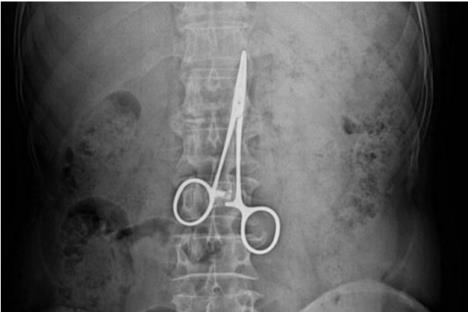

Sud je doneo ovu presudu jer je nesrećni pacijent devet godina u stomaku nosio hirurške makaze, koje su lekari zaboravili u njegovoj utrobi. Čovek je trpeo nesnosne bolove, posle rutinske operacije čira na želudcu, aniko nije znao što je razlog. Slali su ga od jednog do drugog lekara, ali bolovi nisu prestajali.

"Konstantno sam kašaljao. Na kraju sam otišao da snimim pluća i doživio šok. Na snimku su se videle makaze duge 12 santimetara! To su makaze koje se na operacijama koriste za zaustavljanje krvarenja, mislim da im je stručni naziv “pean”. One su mi malo podigle pluća s jedne strane i to mi je izazivalo stalni kašalj", kaže A.P..

Posle detaljnog pregleda ustanovljeno da mu je jedno plućno krilo uvećano, a na snimku se videlo da se makaze nalaze u debelom crijevu(!?). Punih devet godina kroz njegovu utrobu su putovale makaze, prvo kroz tanko crevo, pa onda kroz debelo gde su su se zaglavile.

Sve je to izazivalo velike bolove koje je jadni čovek jedva trpeo. Operativnim putem makze su ukonjene, ali su mu ostale trajne posledice i veštačenjem je utvrđeno da su njegove životne sposobnosti smanjene za 25 posto.